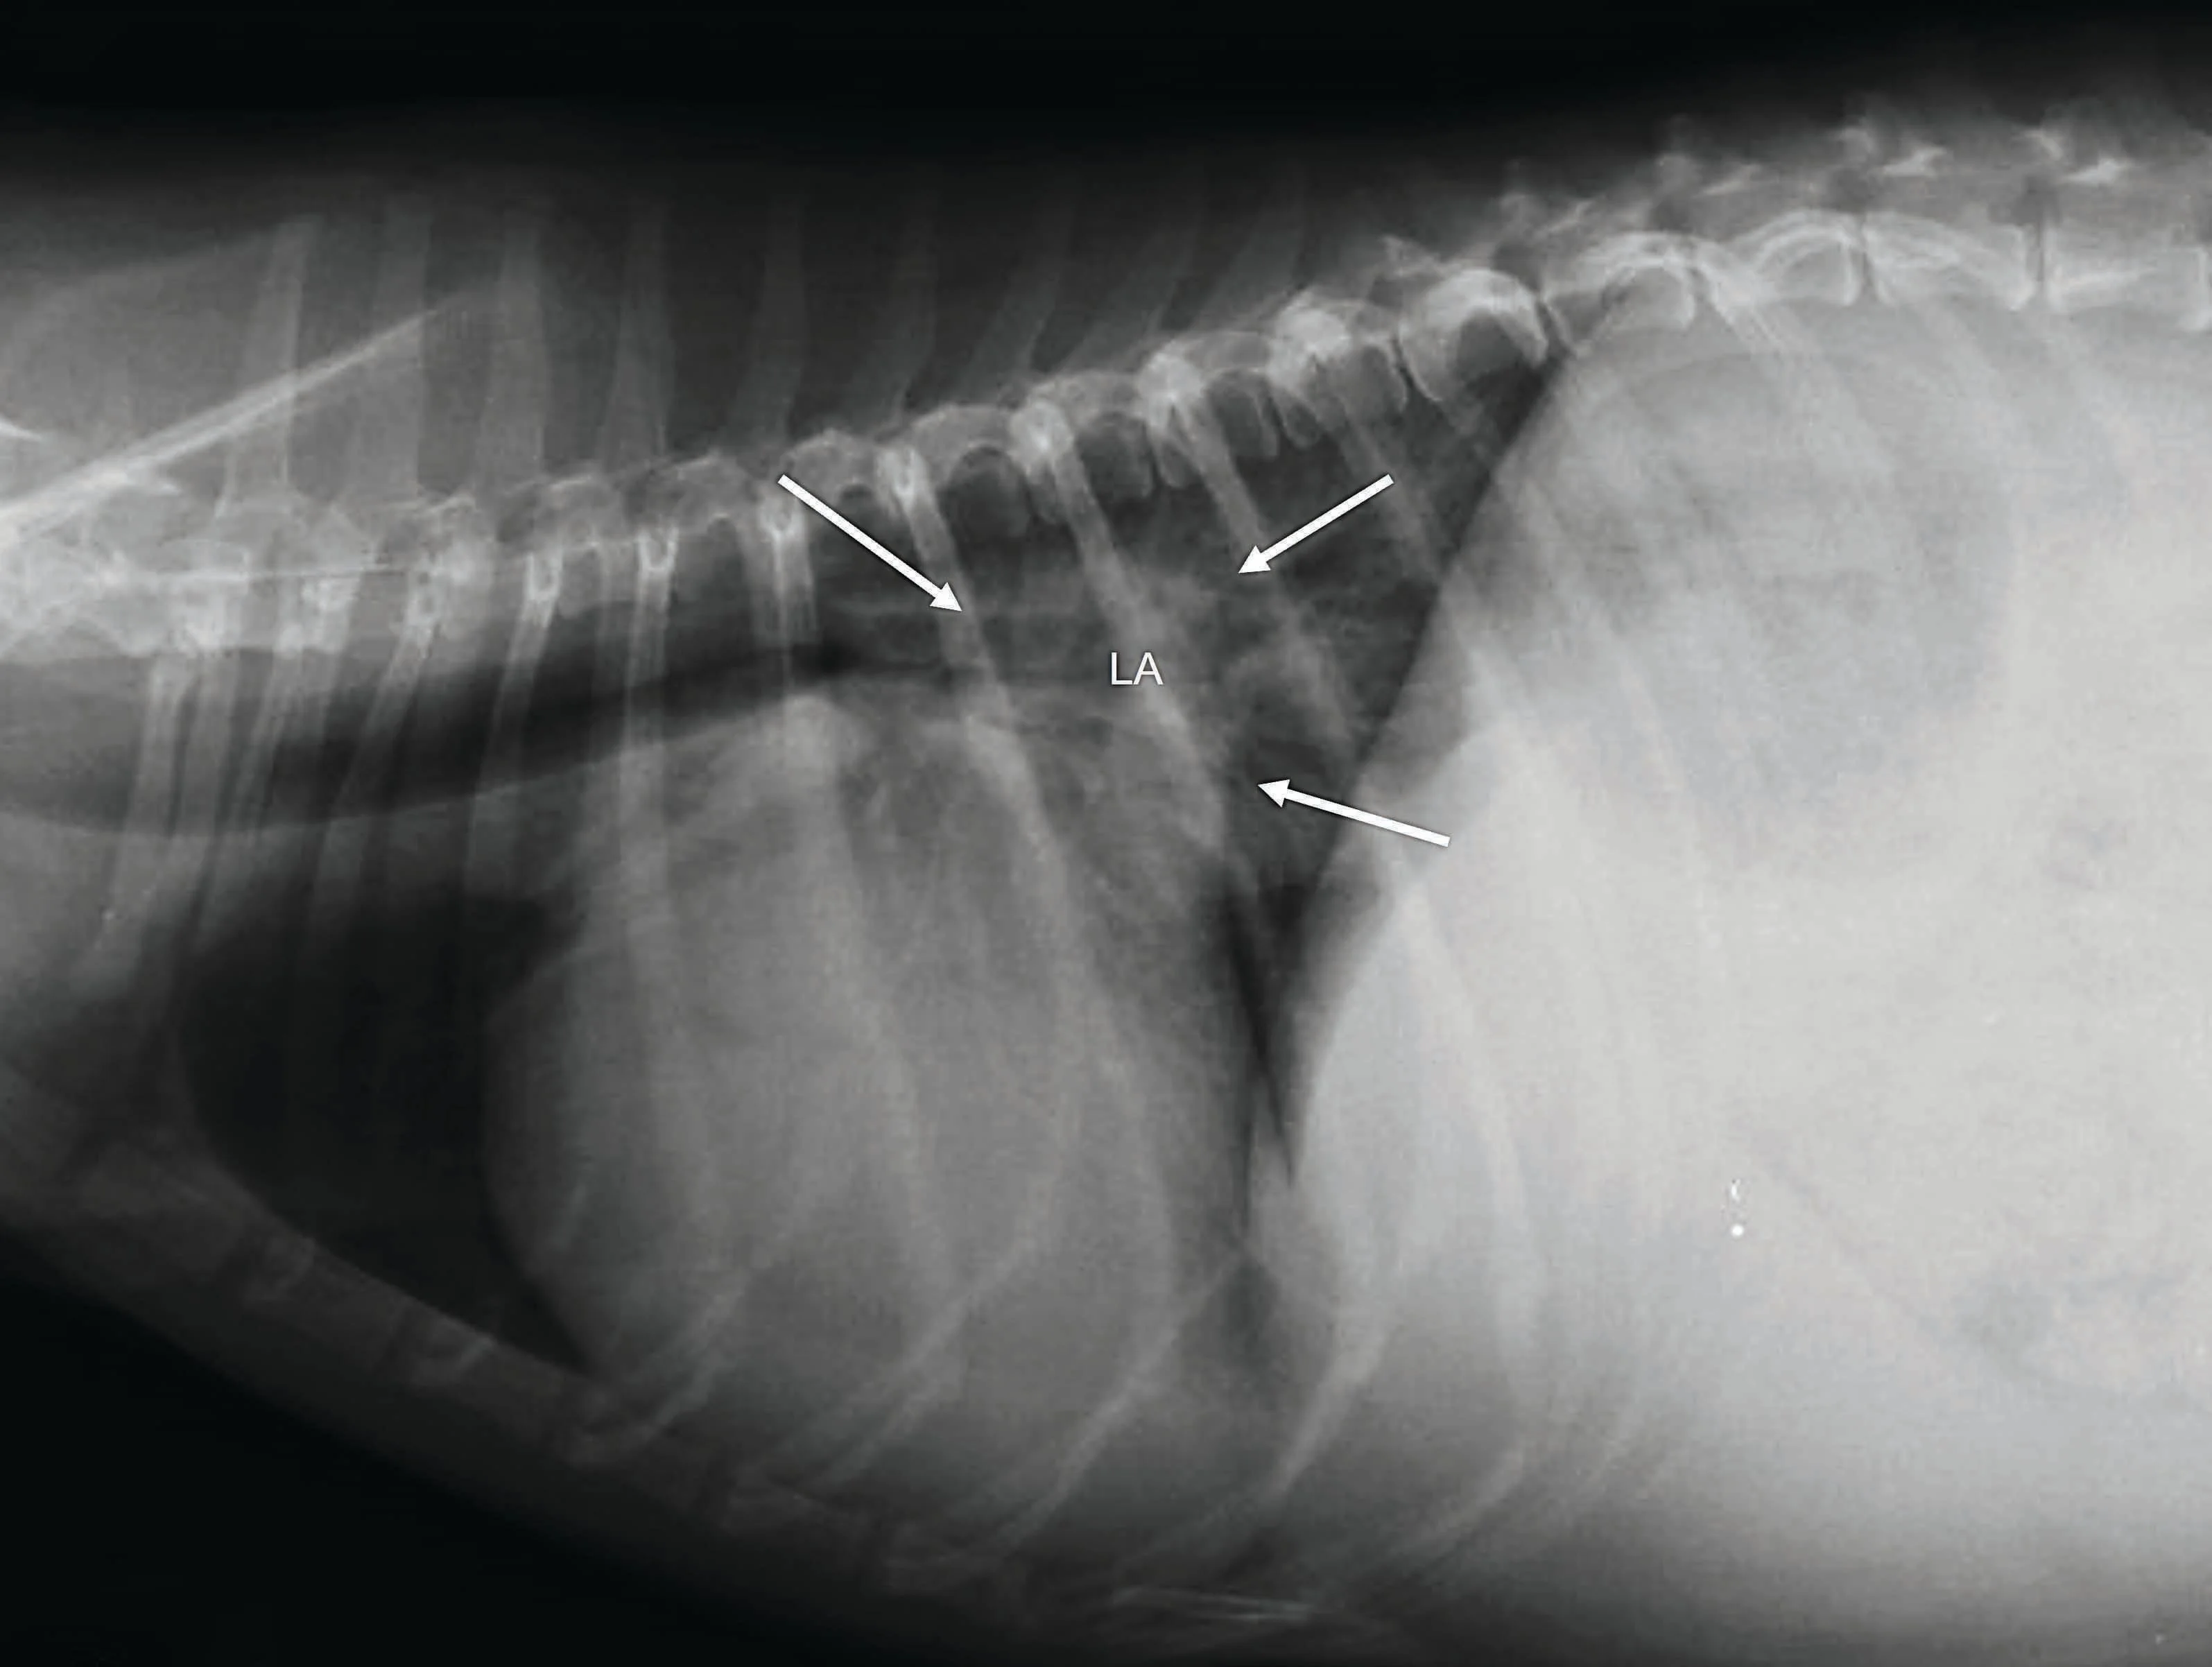

Respiratory Distress: Increased breathing rate and effort are common indicators, suggesting fluid buildup in the lungs or chest cavity, a hallmark of congestive heart failure (CHF).

Fluid Retention: Excessive fluid accumulation in the body is a direct consequence of the heart's failing pump function.

Progression: Heart disease can advance through stages, with Stage D representing end-stage or refractory congestive heart failure, indicating a critical point in the condition's development.